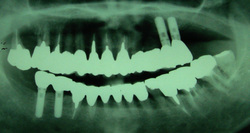

↑インプラント埋入により、義歯からまぬがれ固定することが出来た症例です。

次回は他院でインプラント埋入後に噛み合わせ治療を施した症例を提示します。